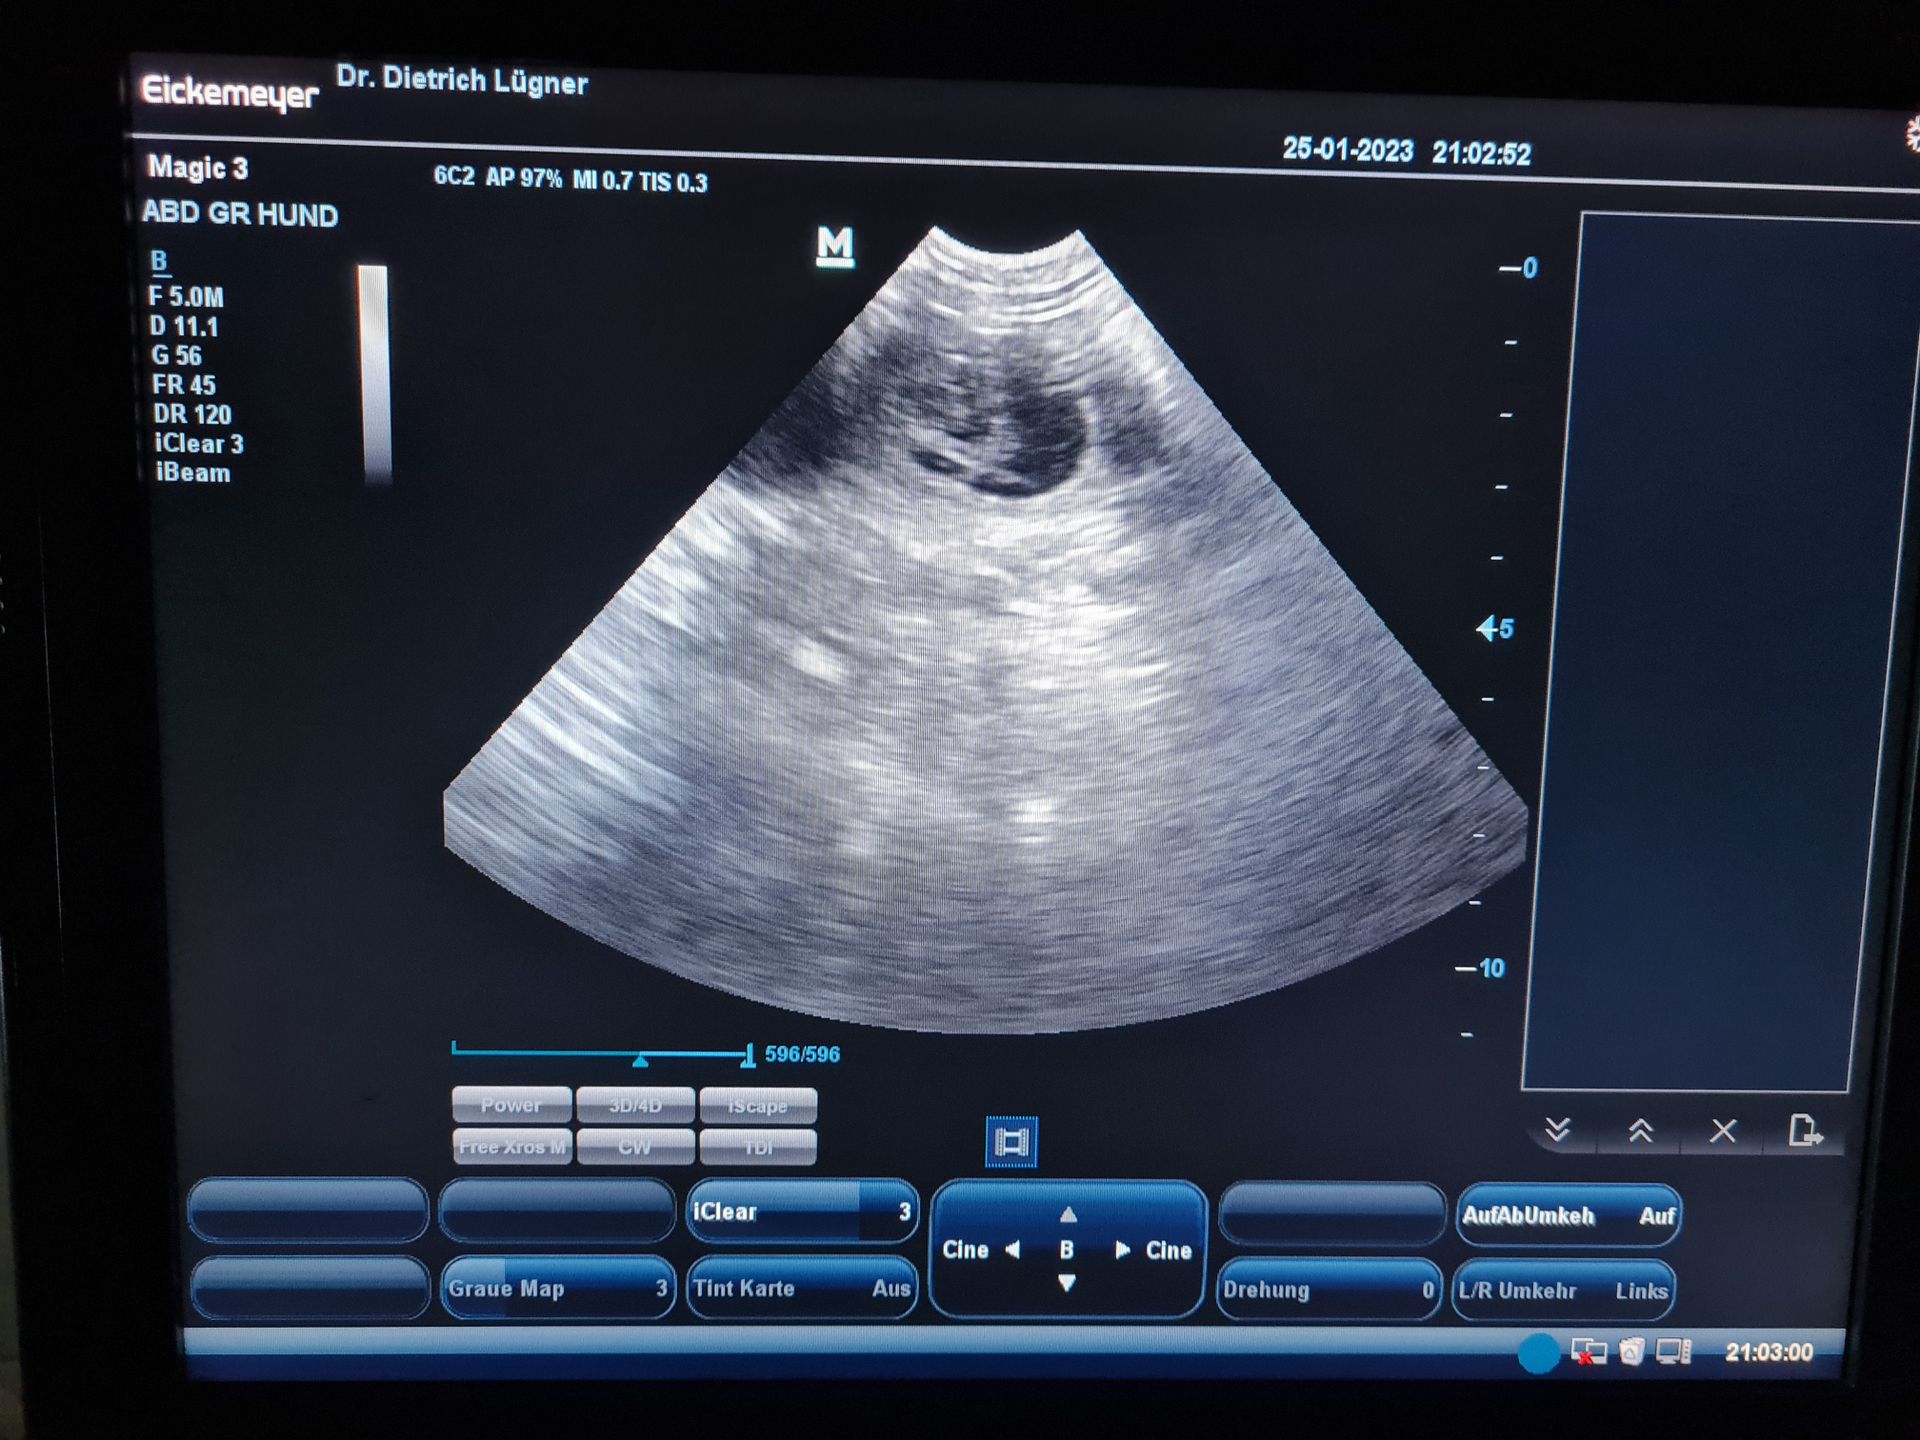

14 Tage noch bis zum voraussichtlichen Wurftag!